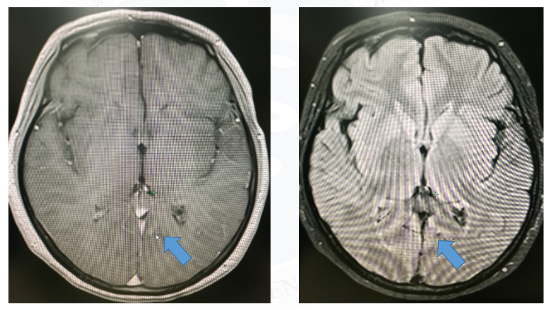

在前两季的病例说栏目中,美宝整理了20例阿美替尼一、二线治疗的经典病例,并邀请相应的研究中心PI进行诊疗点评,以期为临床用药提供指导。本季度病例说仍初心不改,继续对临床中的真实病例进行深层次、多方面地解析,帮助更多临床医生全面了解阿美替尼,为更多患者带来更优治疗方案。 本期病例说特别邀请到北京大学深圳医院MDT团队进行1例EGFR L858R突变合并TP53/ target=_blank class=infotextkey>P53突变NSCLC病例分享。 吴 烜 北京大学深圳医院肿瘤科副主任医师 龙 翔 北京大学深圳医院呼吸科主任医师 谭志博 北京大学深圳医院放射治疗科副主任医师 周凤睿 北京大学深圳医院肿瘤科主治医师 许芹芹 北京大学深圳医院病理科主治医师 单慧明 北京大学深圳医院影像科副主任医师 病史介绍 2020.09.03 颅脑MRI:左侧枕叶异常信号,考虑转移瘤。 全身骨显像:全身诸骨骨盐代谢未见明显异常,建议定期复查。 双锁上淋巴结超声:未见明显异常。 图3颅脑MRI 图4免疫组化 肺癌脑(膜)转移GPA预后评分:3分;脑(膜)转移mol-GPA预后评分:3分。 病例简介

图6颅脑MRI

图13颅脑MRI

1. 该患者因咳嗽咳痰1月余,且加重10天就诊,初诊为右下肺腺癌 (右下肺内、颅脑转移, cT3 Satell N0M1b, IVA期),EGFR exon 21 L858R突变、 TP53 exon 8突变,mol-GPA评分3分,2级高血压。“A+T”治疗13个月后全身多发骨转移,奥希替尼治疗3个月后出现间质性肺炎,更换阿美替尼治疗,截止目前疗效评价PR,安全性良好。